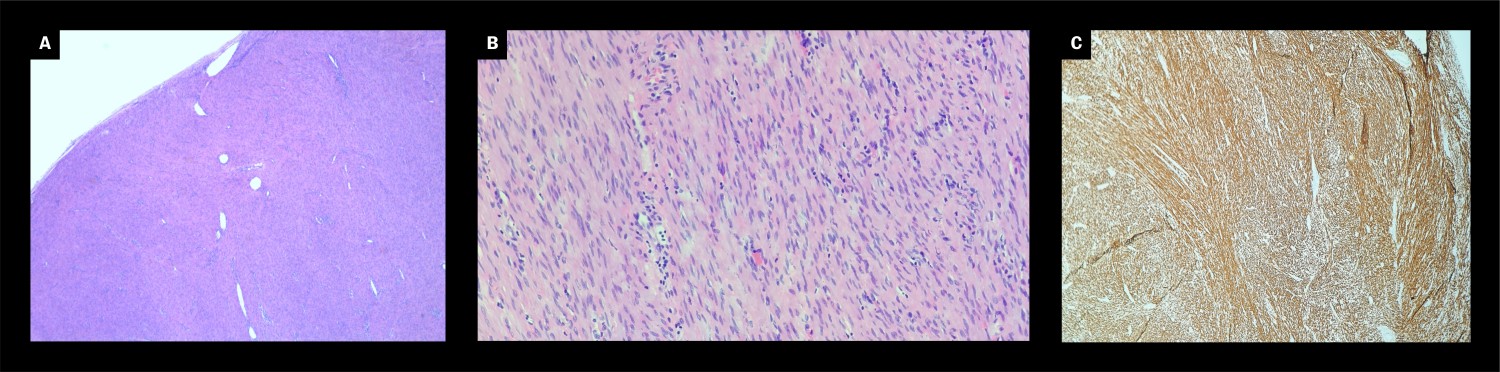

Makroskopisk undersøkelse viste en velavgrenset knute med glatt overflate som målte 5 × 4 × 2 cm og veide 23 g. Figur 1 viser den gråhvitlige solide snittflaten sett ved gjennomskjæring av tumoren. Ved mikroskopisk undersøkelse ble det sett fasikler av spolformede celler med eosinofilt cytoplasma og elongerte kjerner uten prominente nukleoler (figur 2a og 2b). Det var lite mitoser, og nekrose ble ikke påvist. Dette var forenlig med benign tumor. Tumorcellene var immunhistokjemisk homogent positive for desmin (figur 2c) og i mindre grad for DOG-1, forenlig med glatt muskulær differensiering. Det var lav proliferasjon (Ki-67 < 5 %). SOX10, S-100, CD117 and CD34 var negative i tumorvevet. Dette resultatet utelukket en tumor med nevrogen differensiering (for eksempel schwannom) eller en gastrointestinal stromal tumor (GIST) utenfor tarmen, som ble vurdert som histologiske differensialdiagnoser. Knuten var omgitt av sparsomme kollagenfibre med kapselliknende utseende. Dette funnet bekreftet den kliniske vurderingen om at tumoren var fritt fjernet i sin helhet.